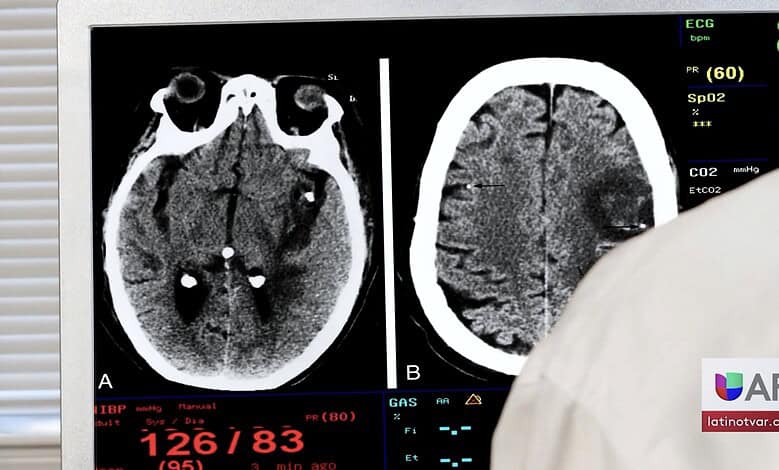

Cada 40 segundos, alguien en Estados Unidos sufre un derrame cerebral.

Y aquí en Arkansas, casi 32 personas son hospitalizadas por esta causa todos los días, lo que significa al menos un caso cada hora.